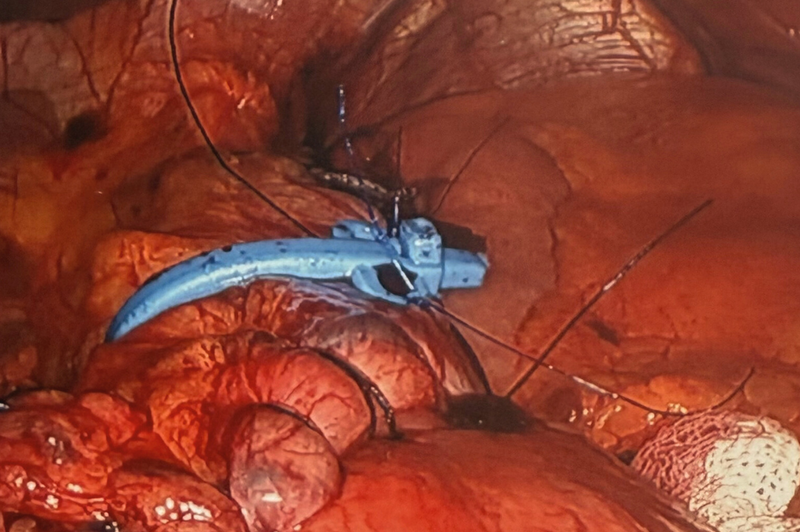

Fundoplication For Acid Reflux

When acid reflux symptoms are severe and the cause is a laxity of your gastro-oesophageal sphincter, then a laparoscopic fundoplication can be performed to improve your reflux symptoms.